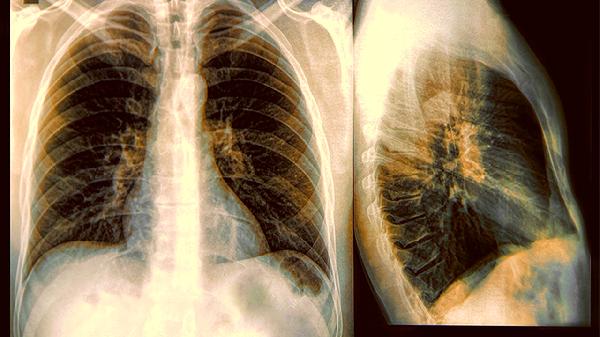

有一种肺癌对烟草有着特殊的"嗜好",它不像普通肺癌那样温和,一旦被它盯上,治疗难度直线上升。这种癌症的生长方式更加狡猾,早期几乎不会露出马脚,等发现时往往已经错过了最.佳治疗时机。

香烟燃烧时释放的大量有害物质就像一支"特工队伍",悄无声息地改变着肺部细胞的基因结构。这些物质不仅会直接损伤DNA,还会削弱肺部自身的防御能力,让癌细胞得以乘虚而入。